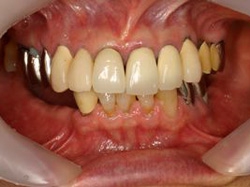

術前口腔内(正面観)

術後口腔内(正面観)もう入れ歯は要らなくなりました。